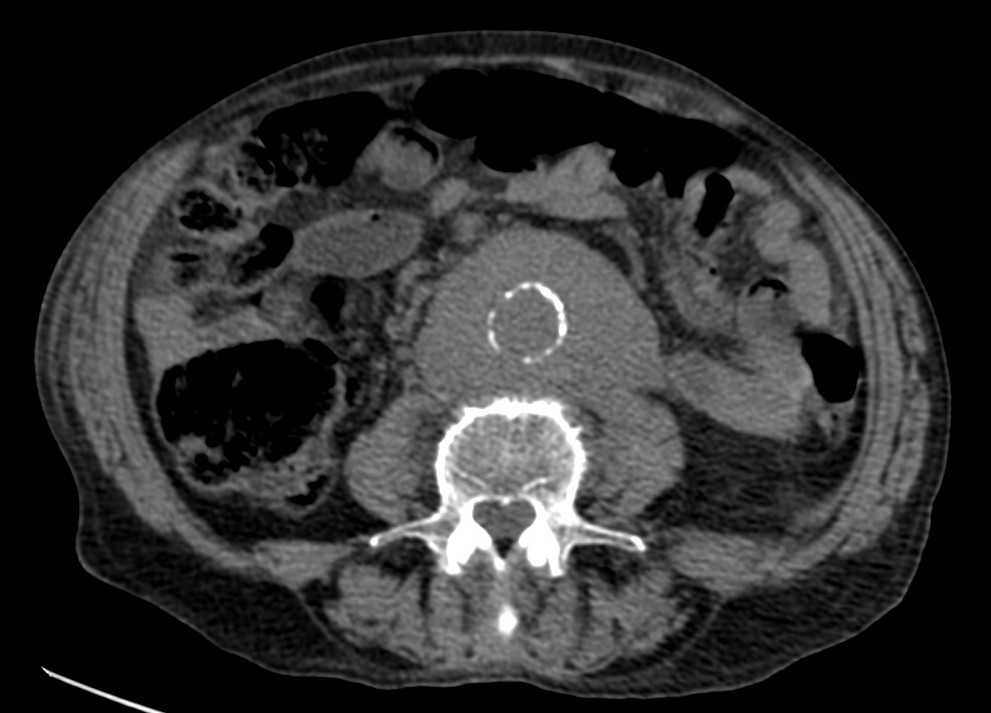

Veamos los hallazgos en una TAC con y sin contraste:

Decimos masa en este caso, aunque se podría pensar que es un sangrado de aneurisma. ¿Por qué no es esta última opción? Observar en primer lugar las paredes de la aorta delimitada por calcio, es decir, sus paredes están calcificadas. Para que pudiésemos hablar de aneurisma, nuestra masa debería tener el calcio en su perifería, Signo del calcio tangencial, y esto no ocurre. La aorta está calcificada y no está sangrando, lo cual se ve reforzado por el hecho de que la masa rodea de una manera uniforme y armoniosa la aorta; un sangrado no sería tan regular, no rodearía de una manera tan perfecta la arteria y además habría predominio de sangrado hacia algún lado de nuestra aorta. Solución: Estamos ante un linfoma.